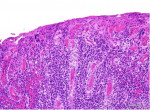

Histologic examination of the specimen from the attached gingiva exhibited erosion of the surface epithelium and supporting intense inflammatory cell infiltrate, predominantly composed of plasma cells (Figure 2). The specimen was covered by fibrinous deposits and supported superficial dilated blood vessels engorged with erythrocytes interspersed by occasional vertical streaks of residual epithelial cells exhibiting uniform basophilic nuclei surrounded by variable amounts of eosinophilic cytoplasm. With an indistinct basal layer, the lamina propria supported an intense inflammatory cell infiltrate, chiefly consisting of densely packed sheets of plasma cells with their characteristic eccentric basophilic nuclei with cartwheel-appearing chromatin surrounded by eosinophilic cytoplasm with paranuclear clear zones (Figure 3). The specimen obtained from the left maxillary gingiva presented with severe chronic mucositis with predominant plasma cell infiltrate, epithelial erosion, and stromal eosinophilia, consistent with PCG. The presence of stromal eosinophils is consistent with allergy-based gingival inflammation.22,23 None of the specimens presented with evidence of neoplasia or granulomatosis. The clinical presentation and histopathological features led the authors to a diagnosis of PCG.